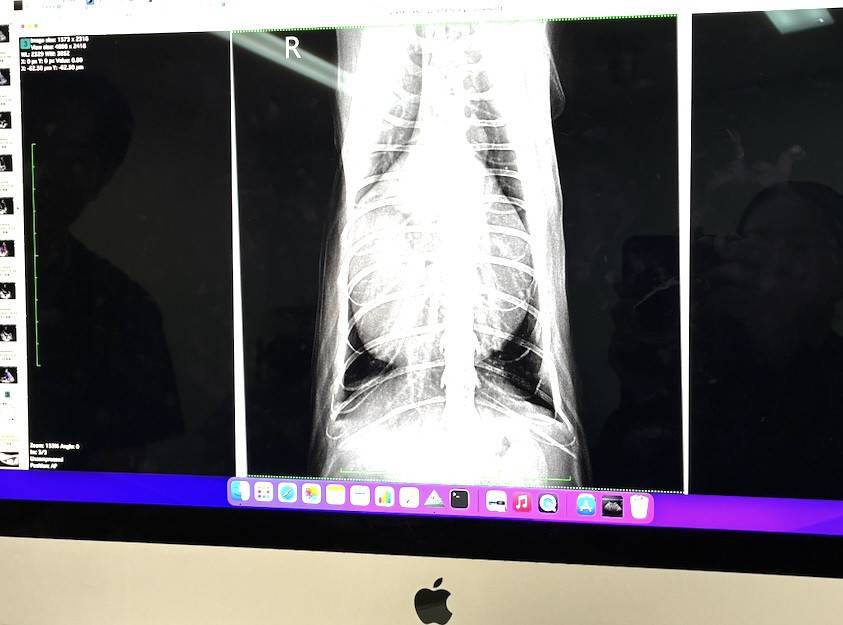

先天性の奇形で「腹膜 心膜 横隔膜ヘルニア」と診断がつきました。通常は去勢手術時のレントゲン検査で、幼猫の頃に気付く事が多いようですが、そんなに進行していなかったのか?地方の病院だとレントゲンせず去勢する所もあるのだとかで。 とにかくシニア手前の現在6歳!で見つかりました。(心臓の周りに臓器がきてて心臓が大きく見えたが、原因は横隔膜に穴あり)

その時のレントゲンでわかりました。

横隔膜ヘルニアの手術前にCT検査も受けております。

検査結果、穴から飛び出した臓器に肺が潰され、4分の1ほどしか機能していませんでした。